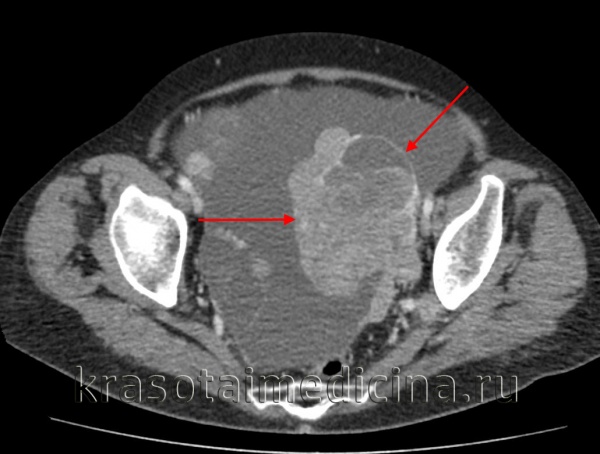

- Лучевые методы. Абдоминальное УЗИ половых органов с дополнительным применением трансвагинальных, внутриматочных и ректальных датчиков, цветной допплерометрии позволяет обнаружить признаки злокачественного роста (неравномерность структуры, наличие множества беспорядочно расположенных перегородок, нечёткость контура, гиперваскуляризация, асцит). Для более точного исследования первичной опухоли, а также с целью выявления метастазов в матке, печени, лёгких, селезёнке могут назначаться КТ и МРТ малого таза, брюшной полости, грудной клетки. Для обнаружения опухолевого поражения толстой кишки применяется колоноскопия.

- Методы визуализации. С помощью трансвагинальной эхографии (УЗИ), МРТ и КТ малого таза выявляется объемное образование неправильной формы без четкой капсулы с бугристыми контурами и неодинаковой внутренней структурой; оцениваются его размеры и степень распространенности.